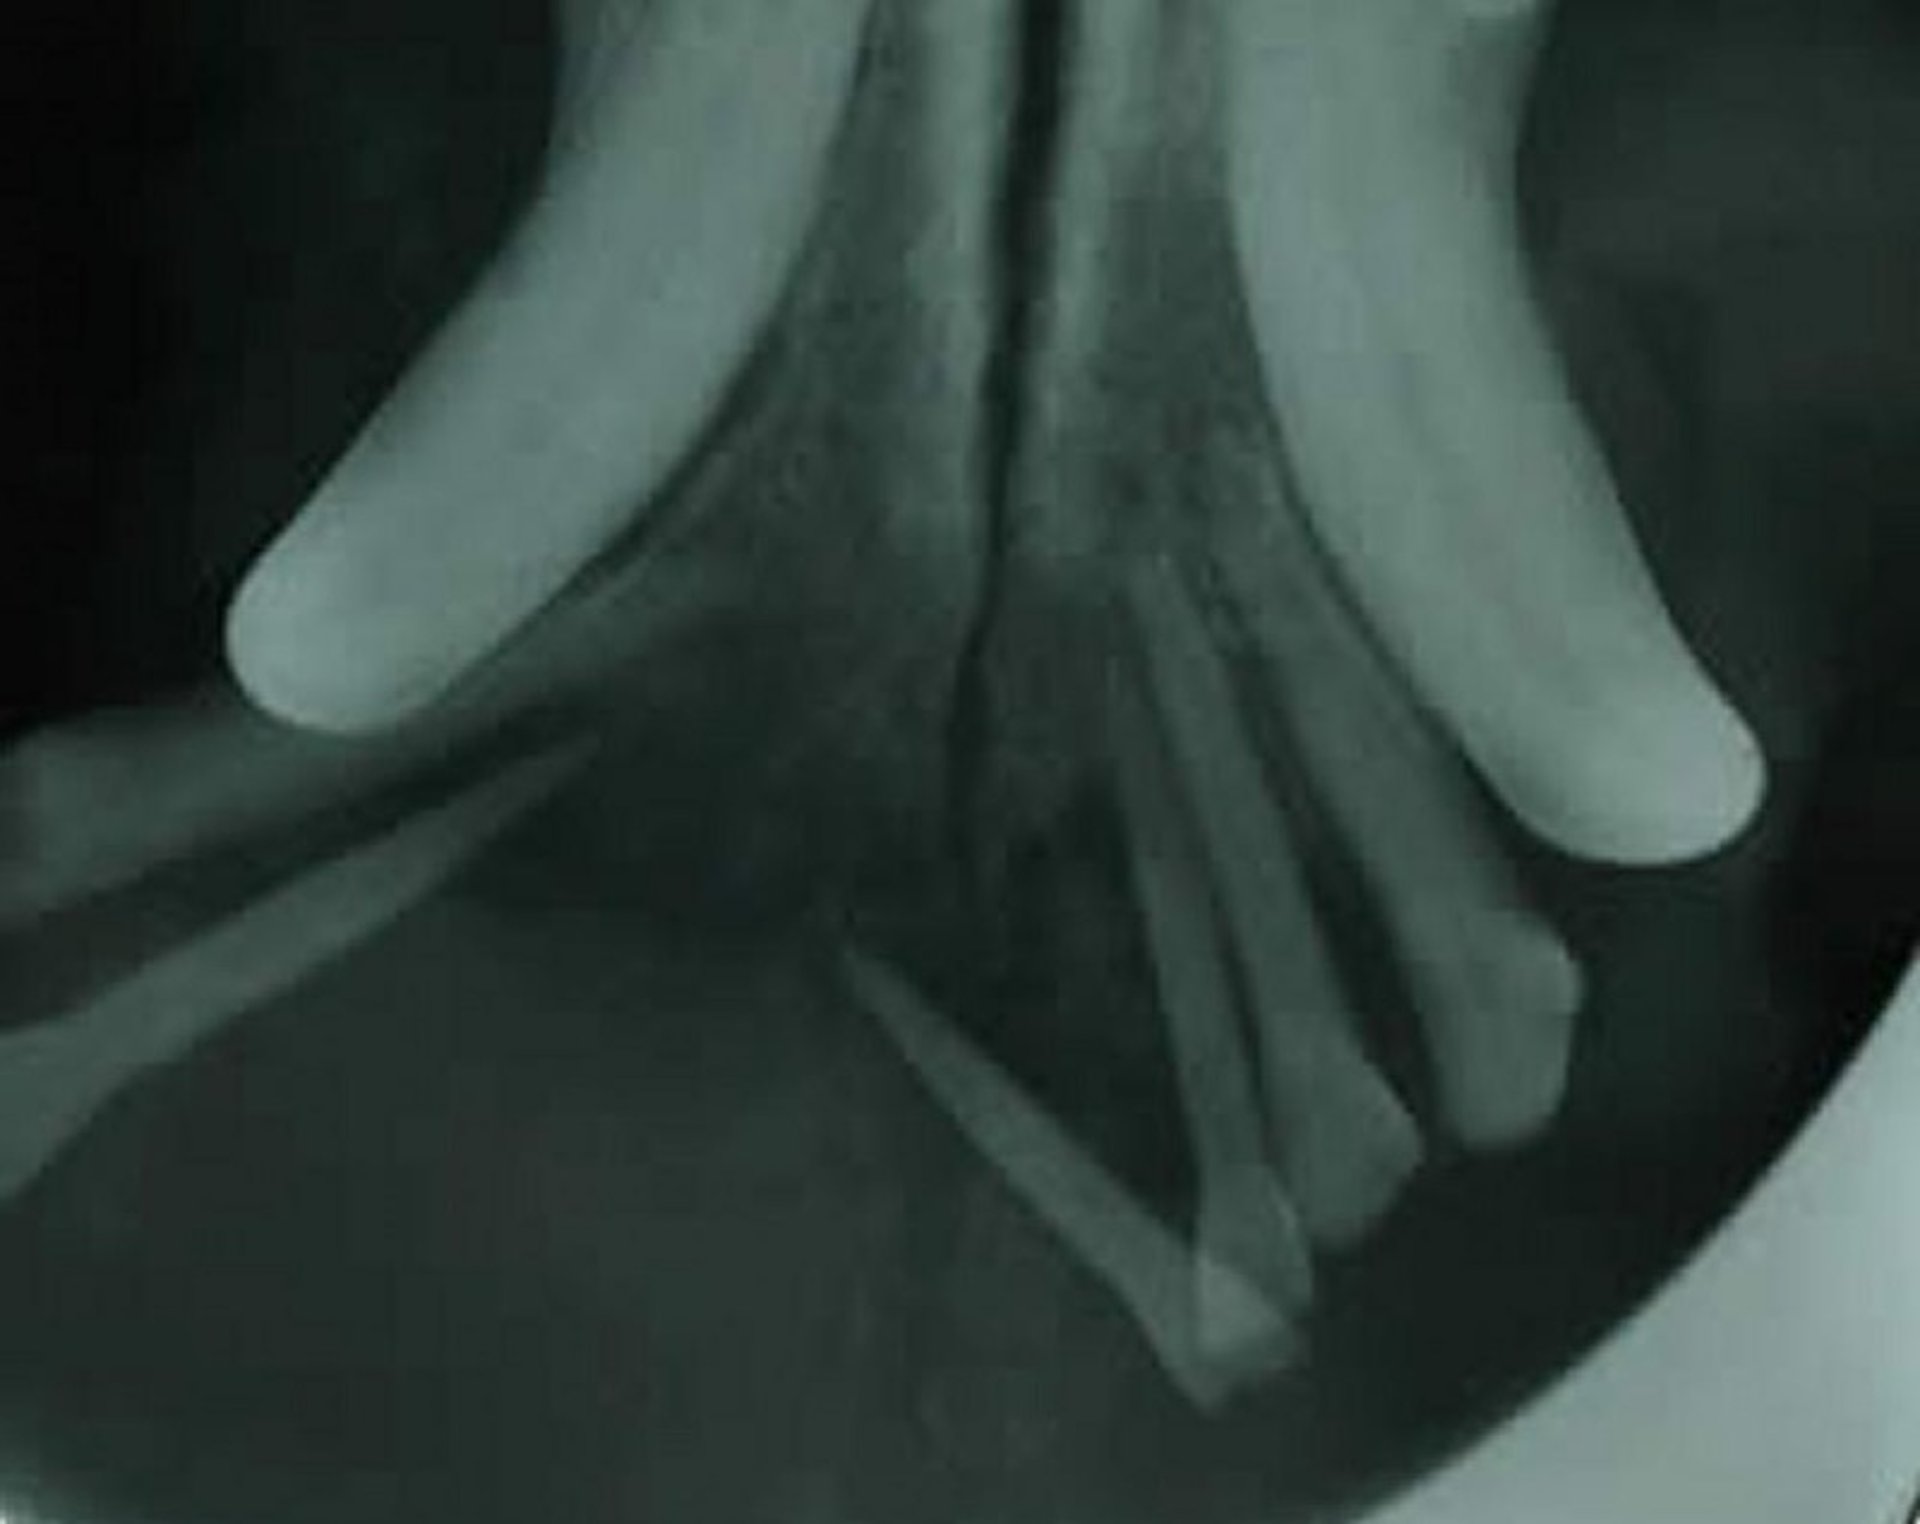

Intraoral radiograph of the rostral mandible with canine acanthomatous ameloblastoma. Note the lack of bone supporting the mandibular incisor teeth. In addition, note the displacement of the incisor teeth, indicative of a likely neoplastic process.

Courtesy of Dr. Ben Colmery III.